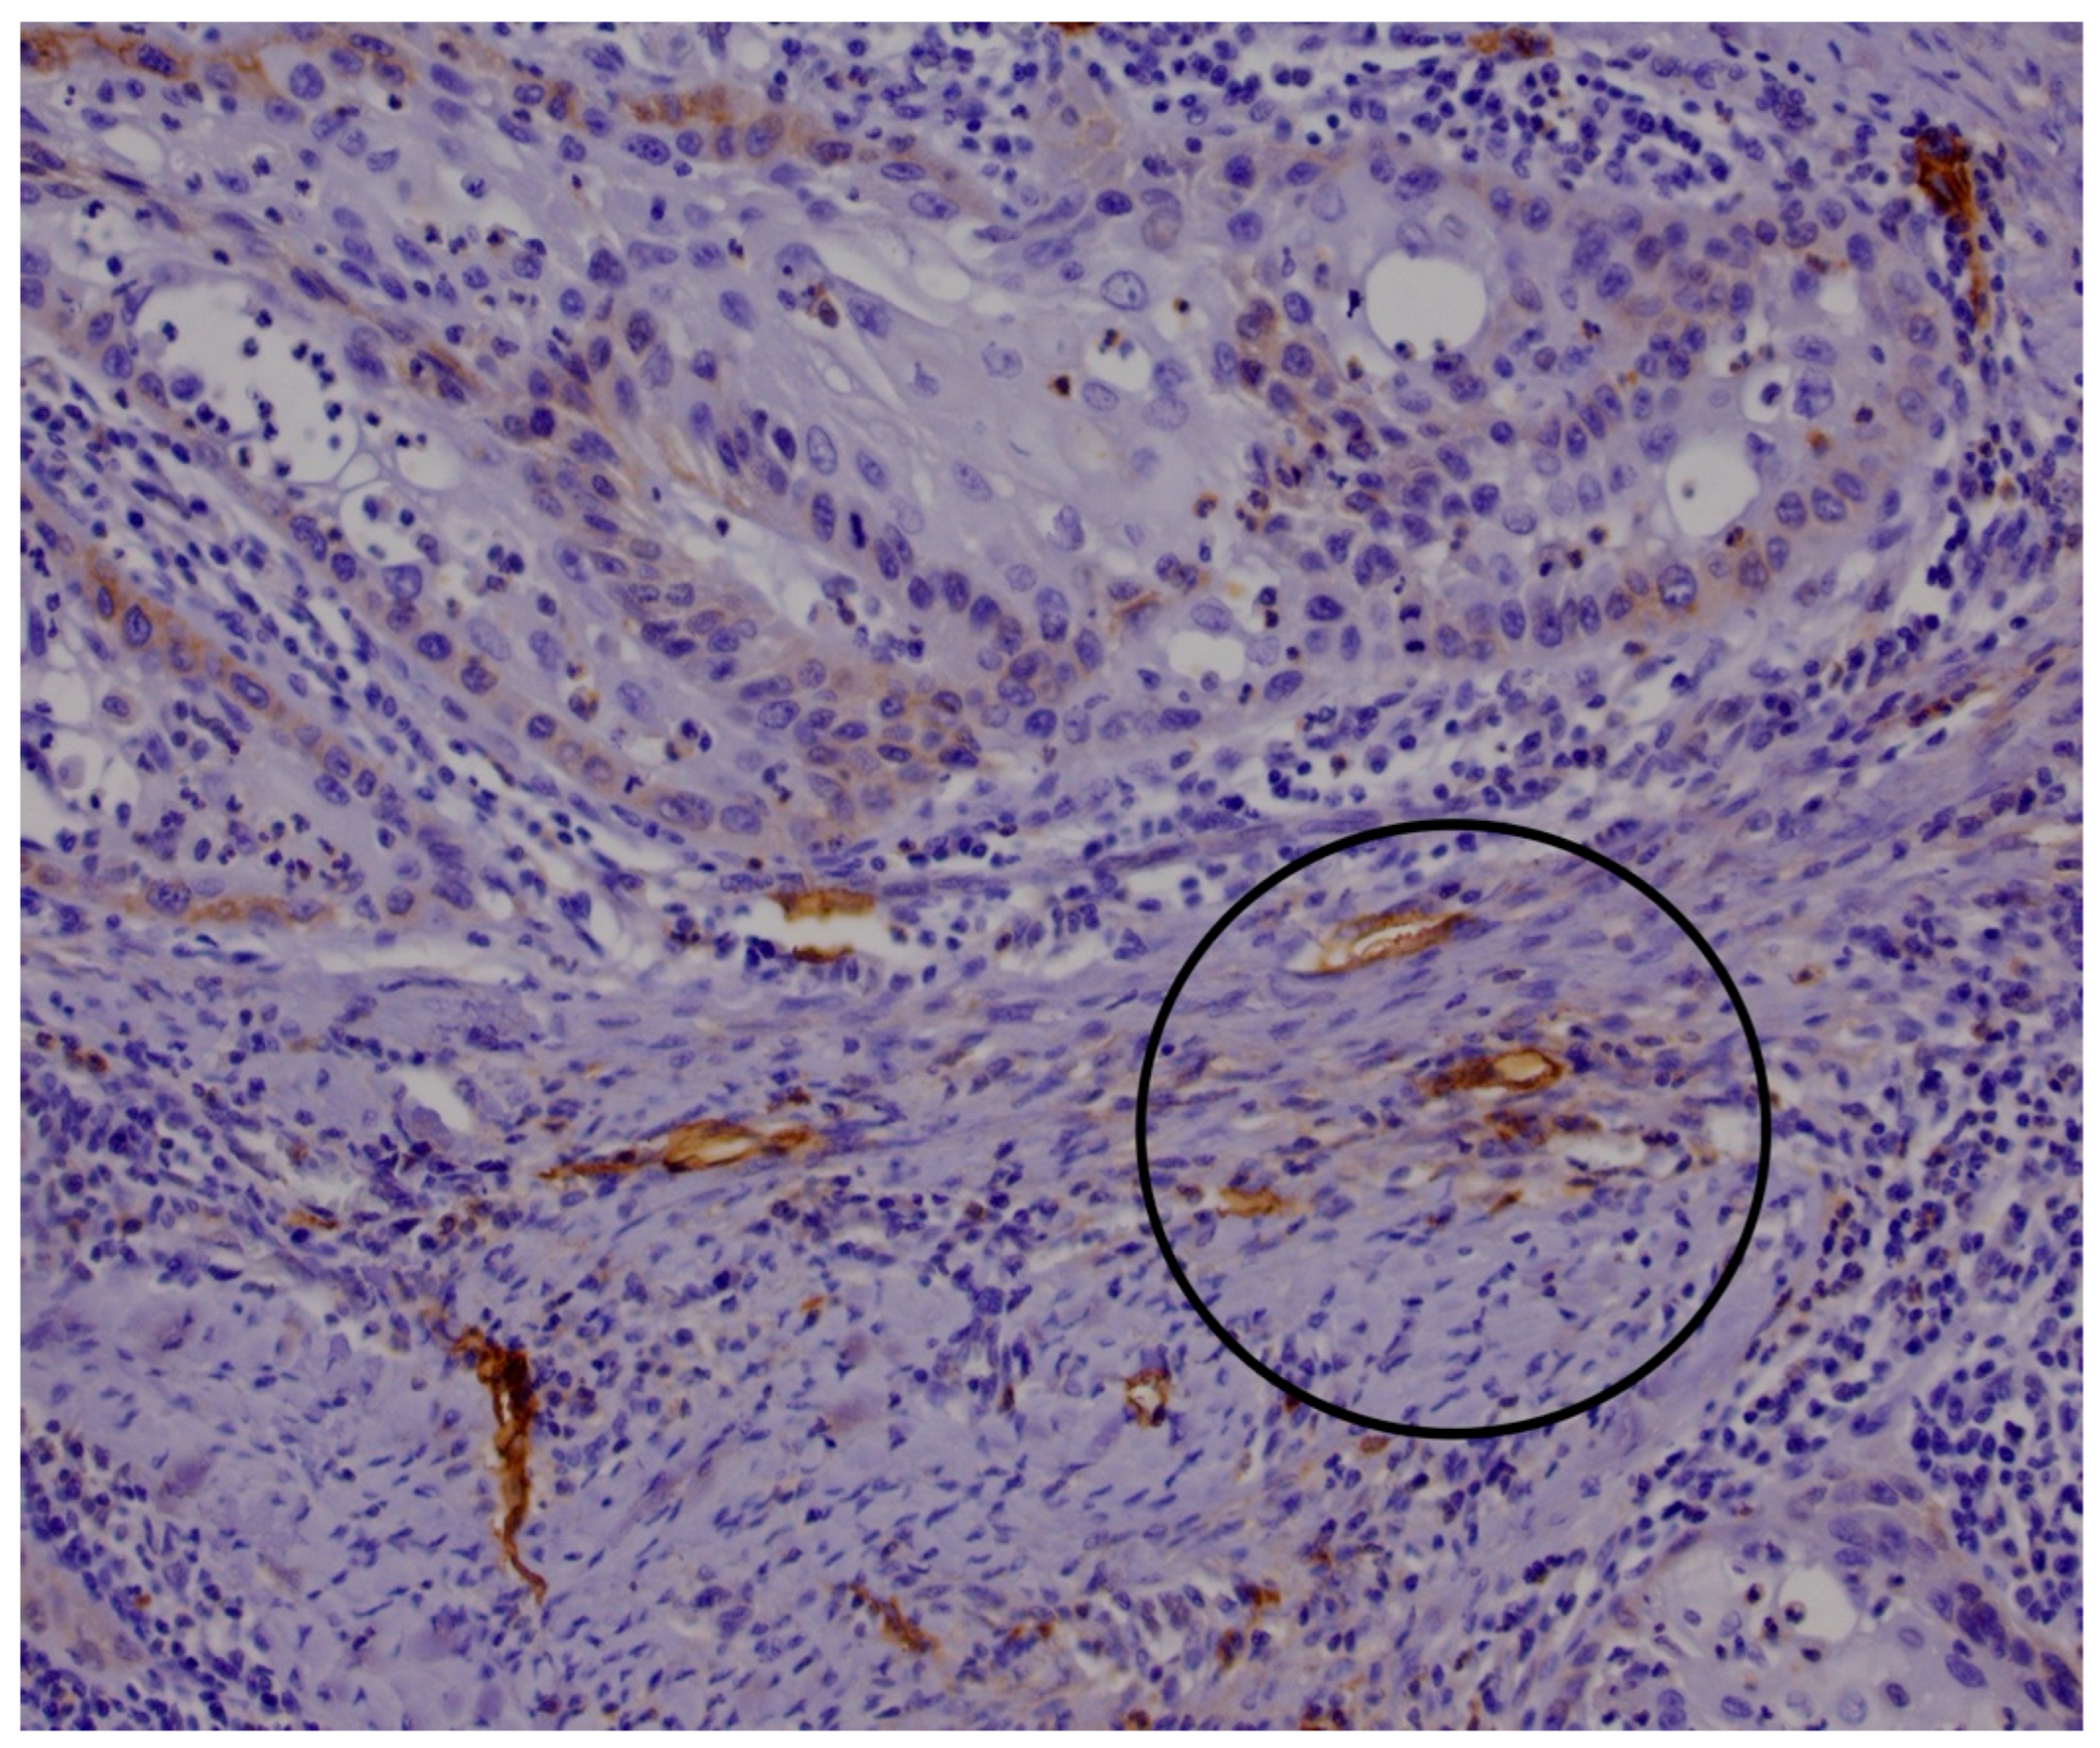

2.1. Histological and Immunohistological Analysis

- Marinho, V.F.Z.; Sanches, F.S.F.; Rocha, G.F.S.; Metze, K.; Gobbi, H. D2-40, a Novel Lymphatic Endothelial Marker: Identification of Lymphovascular Invasion and Relationship with Axillary Metastases in Breast Cancer. J. Bras. Patol. E Med. Lab. 2008, 44, 45–50. [Google Scholar] [CrossRef]

- Agarwal, D.; Pardhe, N.; Bajpai, M.; Gupta, S.; Mathur, N.; Vanaki, S.S.; Puranik, R.S.; Mittal, M. Characterization, Localization and Patterning of Lymphatics and Blood Vessels in Oral Squamous Cell Carcinoma: A Comparative Study Using D2-40 and CD-34 IHC Marker. J. Clin. Diagn. Res. JCDR 2014, 8, ZC86–ZC89. [Google Scholar] [CrossRef]